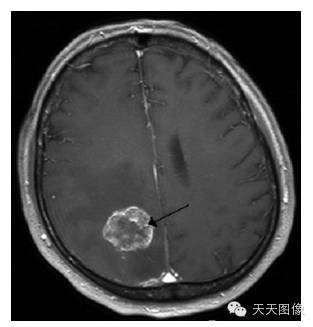

下面只上几张比较中规中矩的肿瘤图像。

上面是一些典型的脑肿瘤图,图中的白块就是肿瘤。为了让大家看的更直观,特地选出来一些比较好分割的图像,但是也并不是什么方法都能分割出来的,就我个人知识而言,不进行任何预处理,没有一种方法可以自动地直接将这些肿瘤都给分割出来。不信可以去问问周边搞图像的人,如果有,请务必告诉我。

下面是我的分割结果,算不上完全自动,但是也是基本上不需要监督。(仔细看肿瘤周围叠加的轮廓,就是分割的结果)

用到的方法就是水平集。